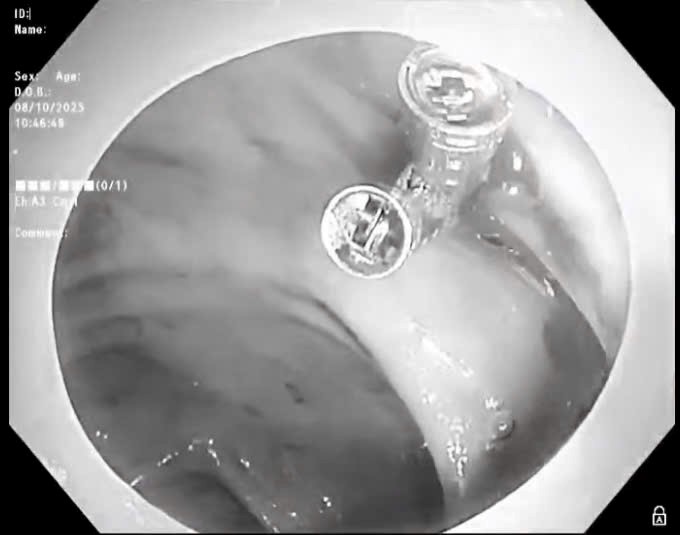

Loại bỏ u mỡ thực quản dưới niêm mạc bằng nội soi, bệnh nhân hết nuốt nghẹn sau 30 phút can thiệp

Thứ Năm, ngày 04/12/2025 15:42Nội soi không chỉ là phương pháp chẩn đoán chính xác mà còn là kỹ thuật can thiệp mang lại nhiều lợi ích cho người bệnh. Mới đây, Bệnh viện K đã tiếp nhận và điều trị thành công cho một trường...